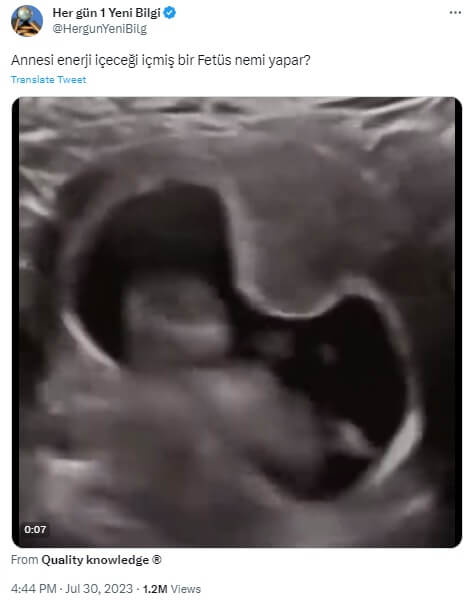

Her gün 1 Yeni Bilgi (@HergunYeniBilg): “Annesi enerji içeceği içmiş bir Fetüs nemi yapar?”

Bahsi geçen video ilk defa 10 haftalık fetüsün hıçkırığını yansıttığını vurgusuyla “10 haftalık fetüs anne karnında çok fazla amniyon sıvısı içtiği için hıçkırıyor” (“10 week old fetus hiccups due to drinking too much amniotic fluid in the mother’s belly“) ifadeleriyle servis edilmiş.

Amniyotik sıvı yüzünden hıçkırık krizine giren bebeğin videosu sonradan enerji içeceği ile ilişkilendirilmiş.

Görüntü 2023 yılı Mayıs ayında uzmanları taraması ile erken cinsiyet tahmini ve cinsiyet doğrulaması yapan Nub Teknolojileri (The Nub Techs Ltd.) tarafından paylaşıldıktan sonra yaygınlık kazanmış (Söz konusu şirketin sosyal medya hesaplarında “DM for credit” yazdığı için görüntünün kendileri tarafından kaydedilmediği anlaşılıyor).